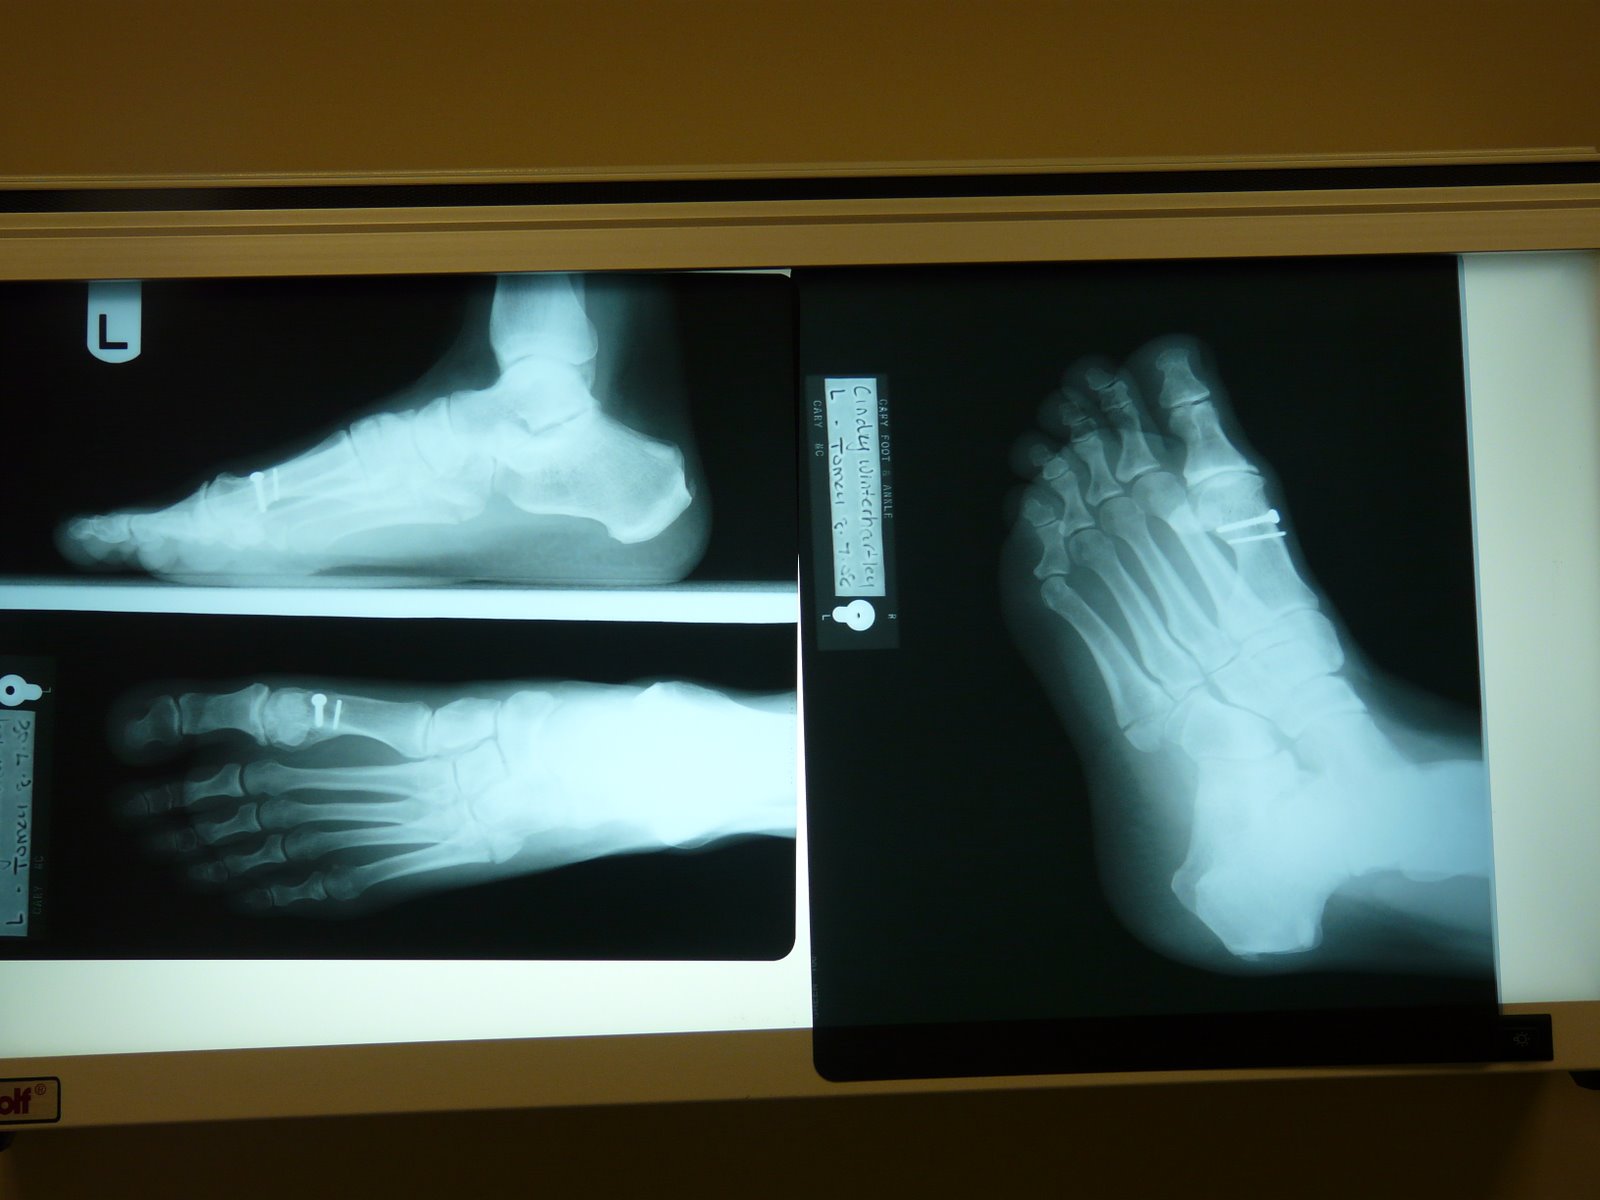

My mood quickly changed after the doctor reviewed the x-rays. I have broken the fifth metatarsal bone. CRUD! Repeatedly the doctor told me I could put absolutely no pressure on my foot for 6-8 weeks. This is very problematic, how does that happen?

Okay, as I was closely examining the x-rays, I couldn’t help but notice what looked like pins in your big toe. Was this broken previously? No pins required for this one?Glad you’re in such great spirit about it! Guess no more late nights dancing at the clubs!–Cuz Matt